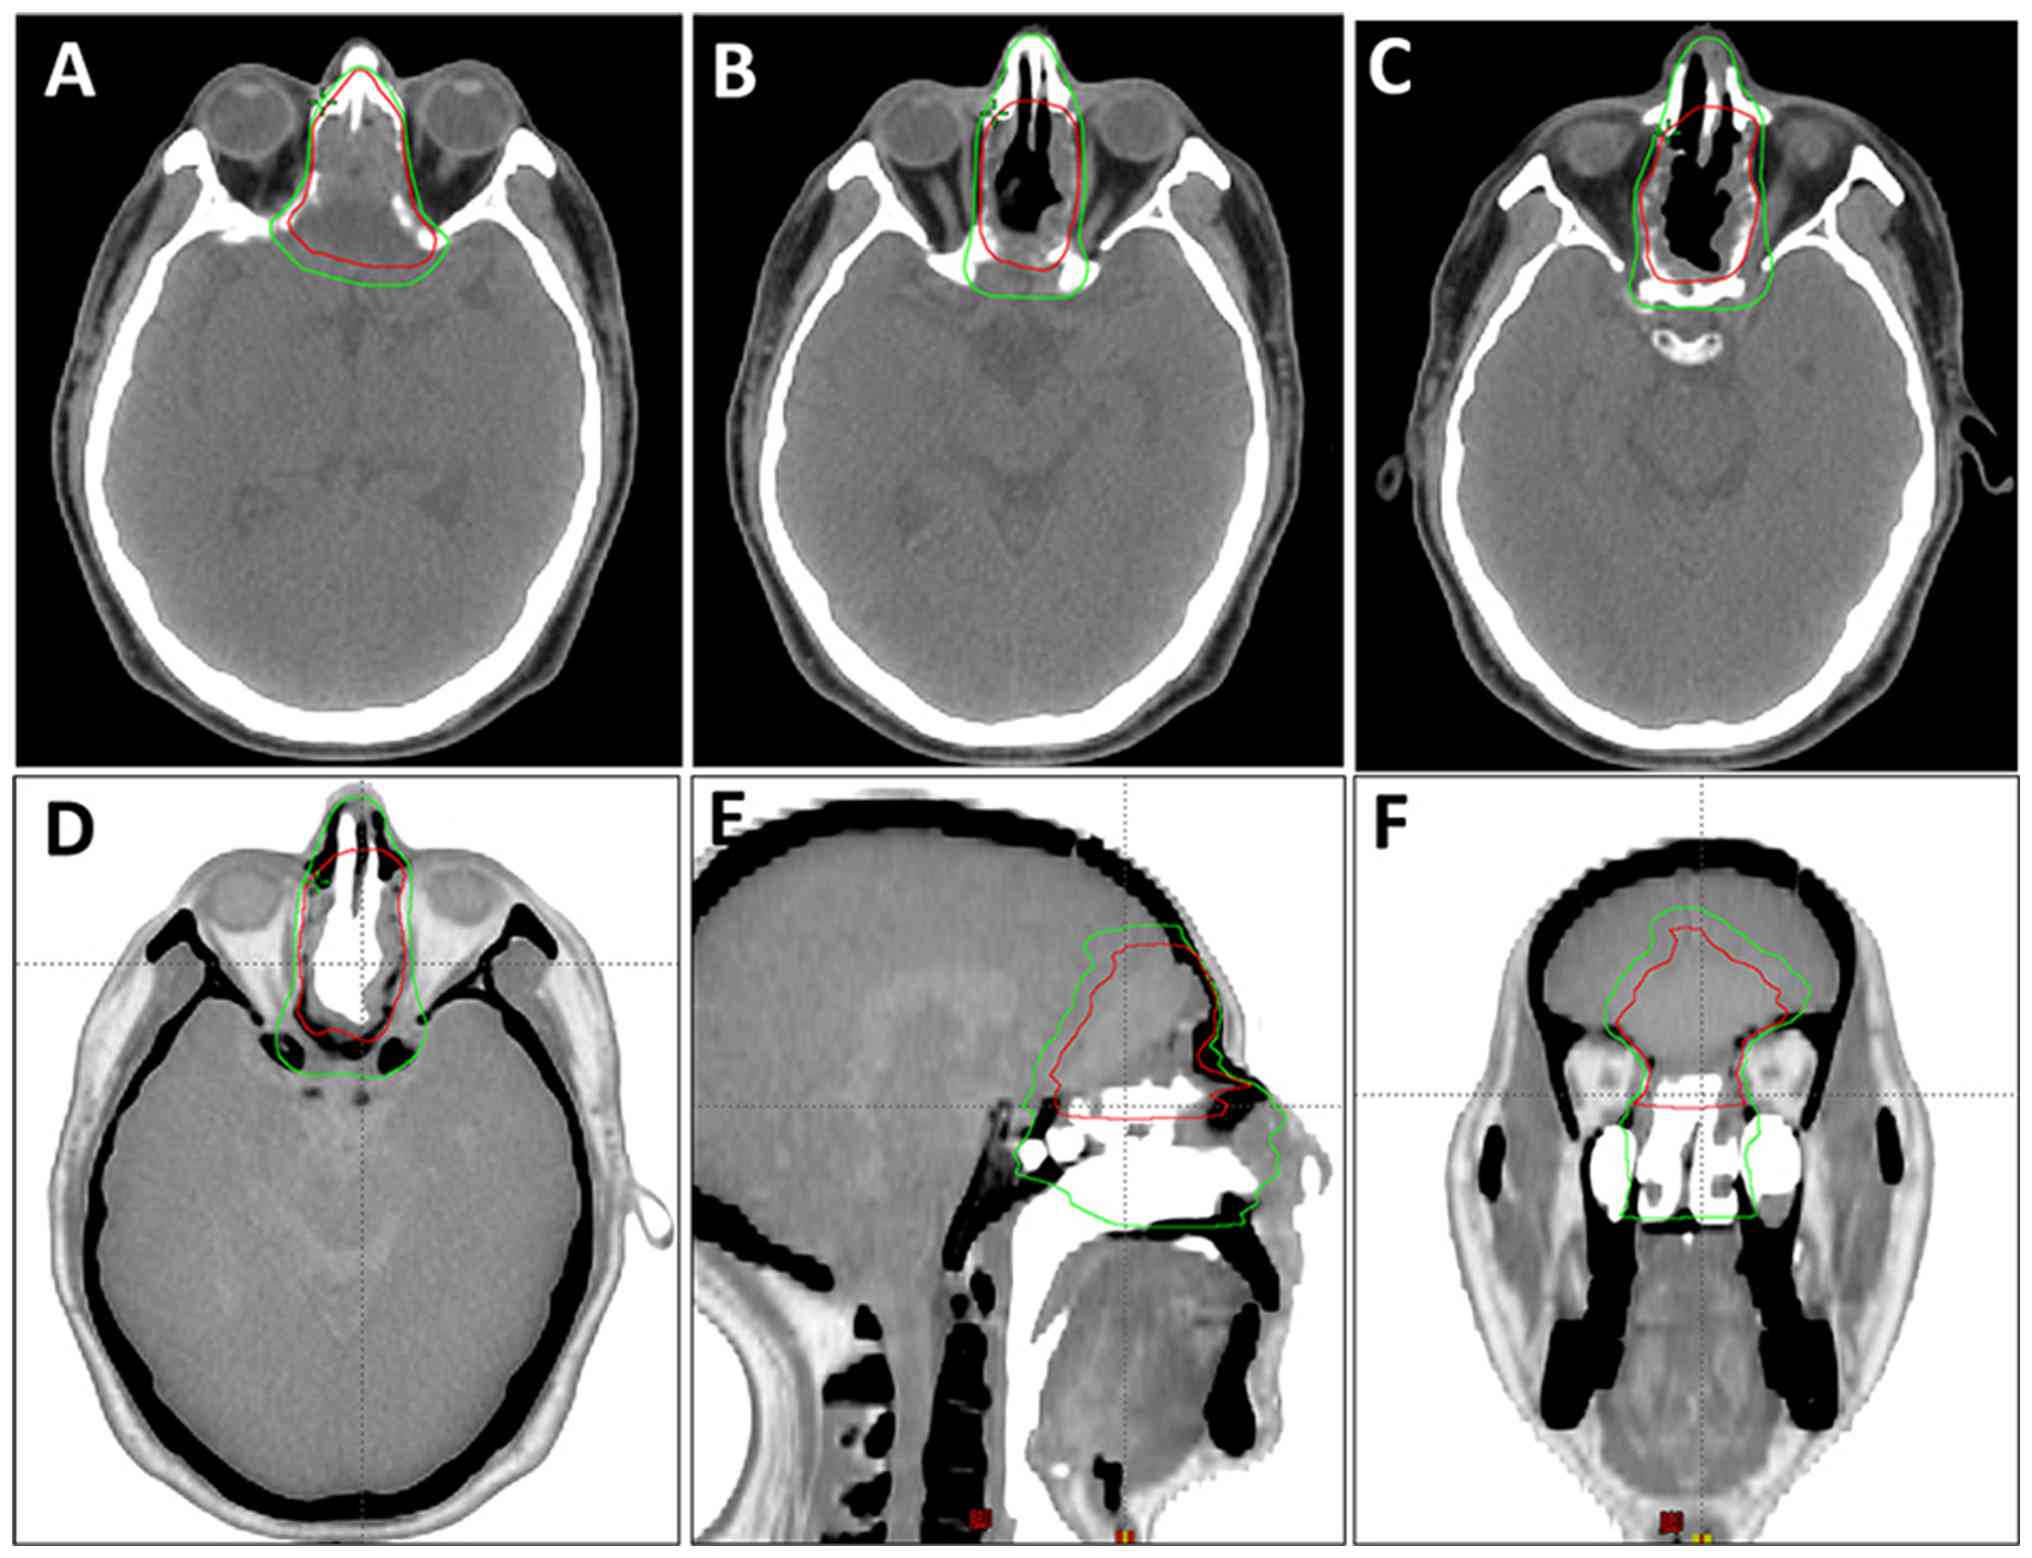

A 60-year-old man presented to West China Hospital, Sichuan University (Chengdu, China) in February 2023 with the primary complaint of progressive loss of vision in the left eye over the past month. Magnetic resonance imaging (MRI) revealed a mass measuring 4.5×2.7 cm located in the region of the ethmoid and sphenoid sinus, with invasion into the intracranial area (Fig. 1). Following a multidisciplinary team discussion, a decision was made to proceed with surgical intervention. The approach selected included a combination of transnasal endoscopy and microscopic craniotomy, accompanied by anterior skull base resection, encompassing the paranasal sinuses, as well as the intracranial and orbital regions. A post-operative pathological analysis indicated the following immunohistochemical findings: CK7(−), CK20(+), CDX2 (+) and villin(+) (Fig. 2), thereby confirming a diagnosis of ITAC. Immunohistochemical staining with CK7, CK20, CDX-2 and villin antibodies (Beijing Zhongshan Jinqiao Biotechnology Co., Ltd.) was performed by the Department of Pathology. Due to the positive surgical margin, adjuvant radiotherapy was administered 2 months later at the General Hospital of Western Theater Command (Chengdu, China). The radiotherapy target volume definitions were as follows: i) Gross tumor volume of the tumor bed (GTV-tb); this encompasses the surgical tumor bed area and any radiographically involved margins visible on imaging. ii) Clinical target volume 1/high-risk clinical volume (CTV-1): This includes the expansion of GTV-tb by 0.5 cm, along with the nasal vestibule, nasal cavity, turbinates and hard palate. However, when the expansion zone approaches critical adjacent structures (such as the optic nerves or cavernous sinus), the margin is reduced to 0.1 cm (Fig. 3). The radiotherapy regimen included a planned dose of 6,480 cGy in 30 fractions (216 cGy per fraction) to the planned GTV-tb (PGTV-tb) [equivalent dose in 2-Gy fractions (EQD2)=65.66 Gy, α/β=10], and 6,000 cGy in 30 fractions (200 cGy per fraction) to the planning CTV-1 (PTV-1) [EQD2=60.00 Gy, α/β=10]. Due to concerns about potential injury to the optic nerve, the patient and their family decided to shorten the radiotherapy course to 25 sessions. The final delivered doses were ~5,400 cGy to the PGTV-tb (estimated EQD2, 54.72 Gy; α/β=10) and 5,000 cGy to the PTV-1. Concurrent chemotherapy was administered with a regimen of cisplatin at 30 mg on days 1–2 every week for four cycles (1 week per cycle).

Examples of target volume

delineation. (A-C) Target area contours on axial planes at

different levels of non-contrast computed tomography images. (D-F)

Display of the target contours in (D) axial, (E) sagittal and (F)

coronal views. The red outline represents the gross tumor volume of

the tumor bed and the green outline represents the clinical target

volume 1/high-risk clinical volume.

Figure 3.

Examples of target volume delineation. (A-C) Target area contours on axial planes at different levels of non-contrast computed tomography images. (D-F) Display of the target contours in (D) axial, (E) sagittal and (F) coronal views. The red outline represents the gross tumor volume of the tumor bed and the green outline represents the clinical target volume 1/high-risk clinical volume.